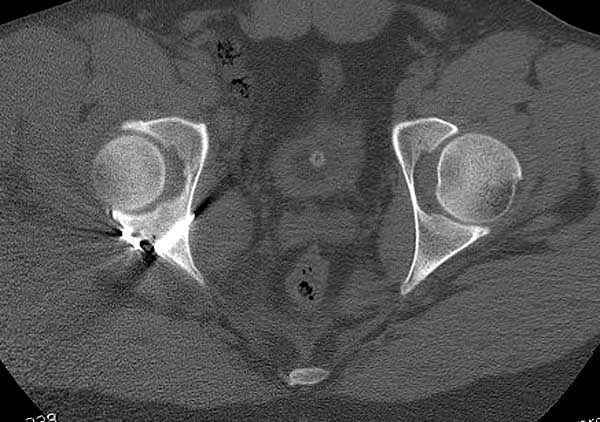

11:50 больной в послеоперационной, рентгенограмма N7, компьютерная томограмма в тот же день N8-10